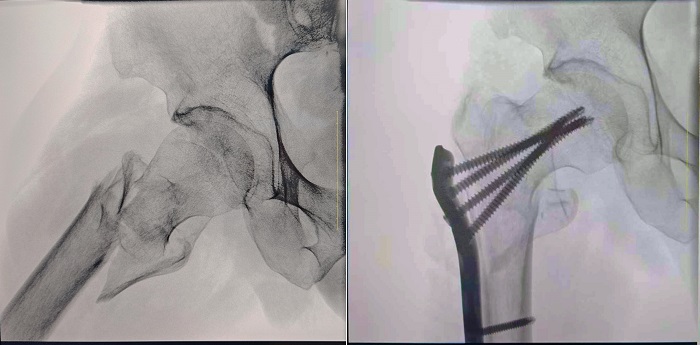

患者:70岁,男

临床诊断:右股骨粗隆间骨折,伴有下肢位移、外旋

术式:右股骨粗隆间骨折切开复位内固定术

一体式移动C型臂拍摄的术前影像

大视野 高清成像 观察更全面

普爱医疗一体式移动C型臂采用30CM×30CM的平板探测器,能够帮助医生全面观察患者断端分离错位情况,确保手术方案的精准制定。